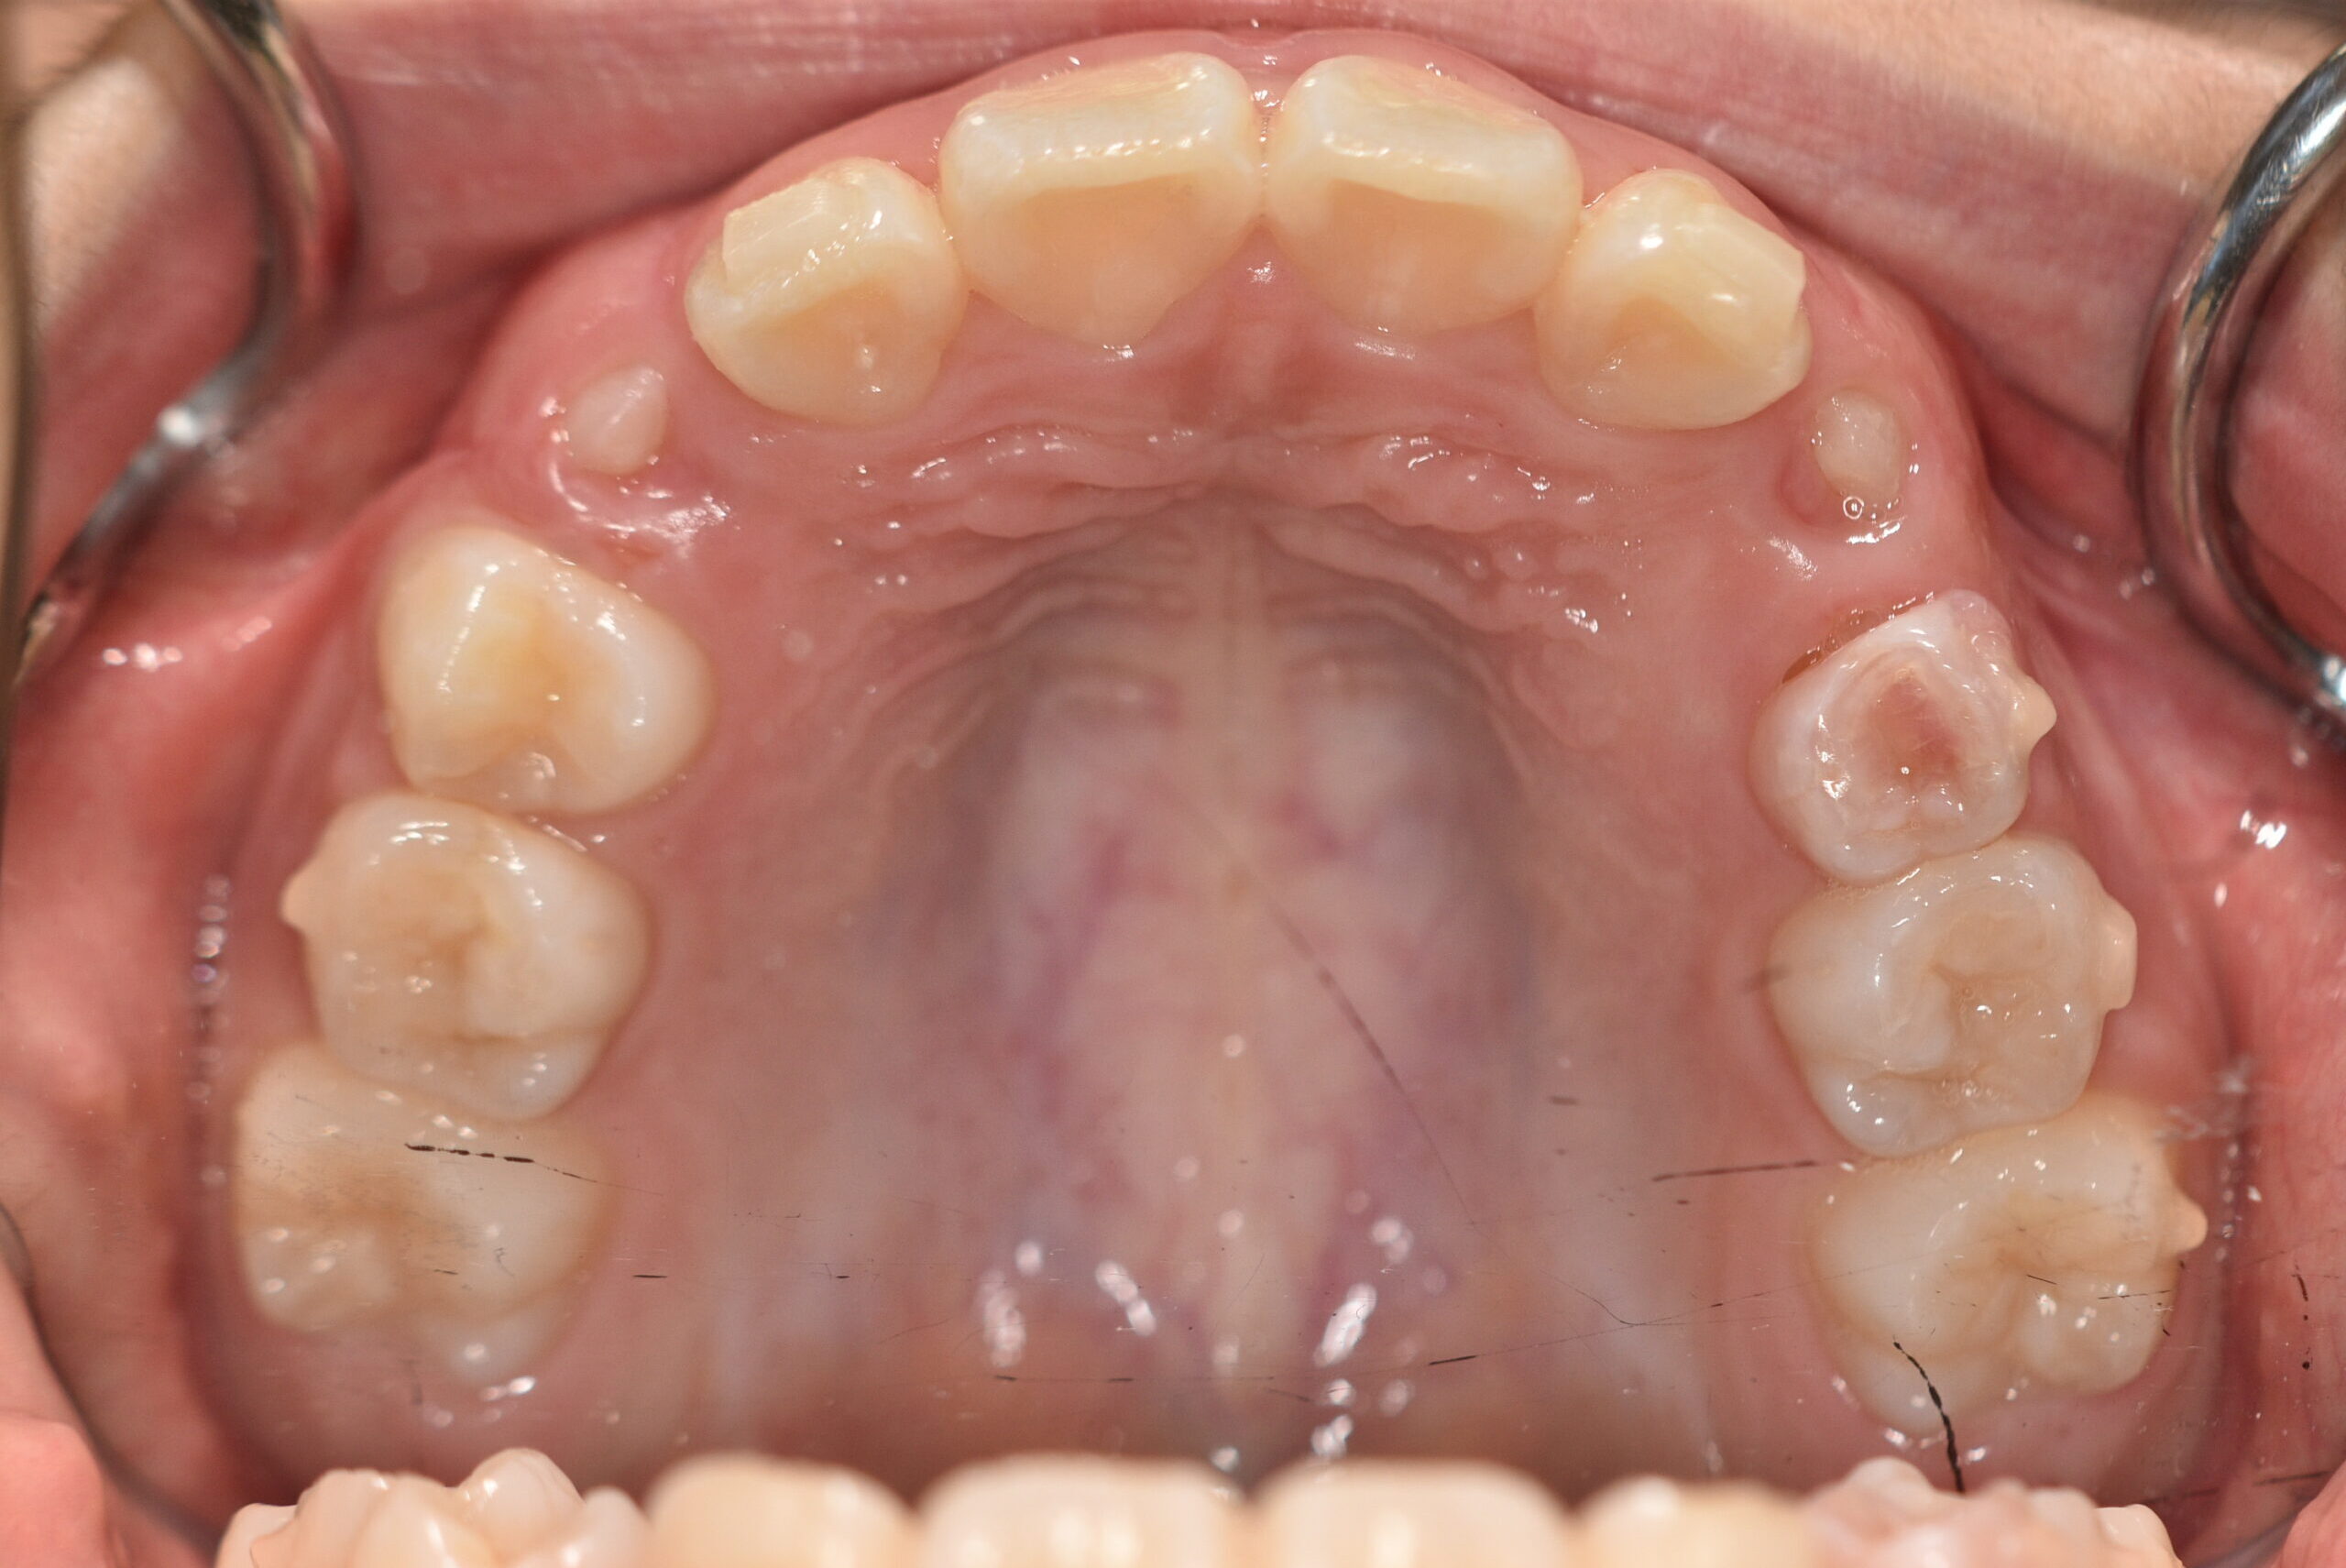

| 治療内容の詳細 | 初診時7歳の女児で、歯のがたつきを気にされ来院されました。 検査の結果、前歯部叢生を伴うアングルⅡ級不正咬合と診断しました。 治療としてはマウスピース矯正(インビザラインファースト)で配列を行い、上下顎の側方拡大と萌出スペースを確保しました。 治療期間は、1年でした。 今後、側方歯生え変わりまで経過観察を行います。 |